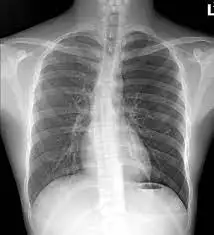

흉부사진

알몸이 흑백으로 드러나 있다

연부 조직은 먼 산으로 물러나 있고

눈부신 하얀 늑골사이로

폐포 잎잎이 떨고 있다